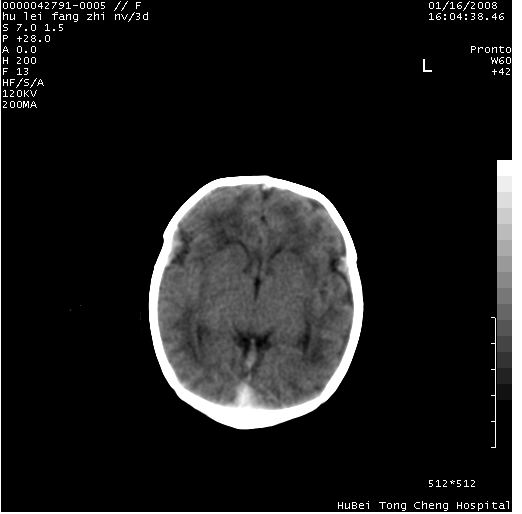

患儿 女,3天。惊跳,纳差。第二胎顺产,羊水ⅱ度。

临床诊断:hie?

颅脑ct轴位平扫(层厚、层距均为7mm),图像如下:

hie合并蛛网膜下腔出血

hie合并蛛网膜下腔出血,五、六脑室形成。

支持hie伴少量蛛血.